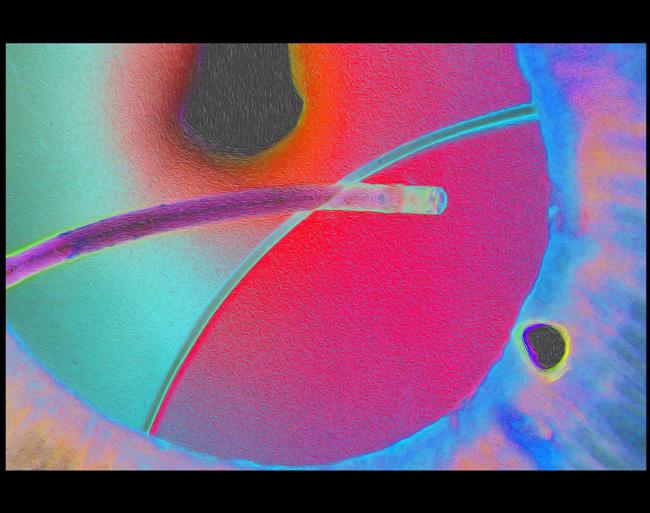

CSABA MARTONYI BEST OF SHOW AWARD and BEST OF STEREO DIVISION The Eye as Art DSEK

Tim Steffens, CRA, OCT-C, FOPS

University of Michigan

Kellogg Eye Center

Ann Arbor, Michigan